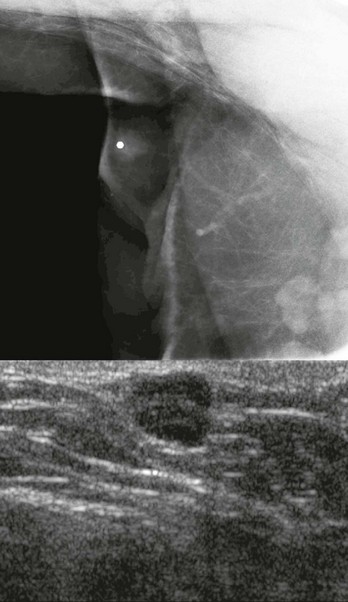

FIGURE 11-18 Metastatic Intramammary Lymph Node.

Although the mammographic appearance is nonspecific, the location and US appearance are consistent with an abnormal intramammary lymph node. Diagnosis: metastatic melanoma.

Melanoma is the most common nonbreast primary neoplasm to metastasize to the breast (Box 11-7).